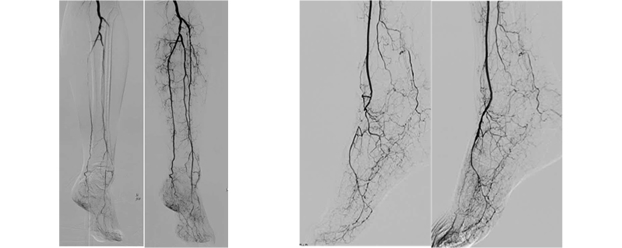

Endovascular Asia is a global multidisciplinary meeting. Our main focuses are total vascular care, peripheral artery disease and critical limb ischemia. Harmonization of endovascular therapy and wound care is also in our territory. This unique meeting has been evolved from Bay Area Endovascular Summit (BEST) to increase our friendship, expand the knowledge of vascular disease and sophisticate endovascular intervention for the treatment of Asian vascular disease patients.